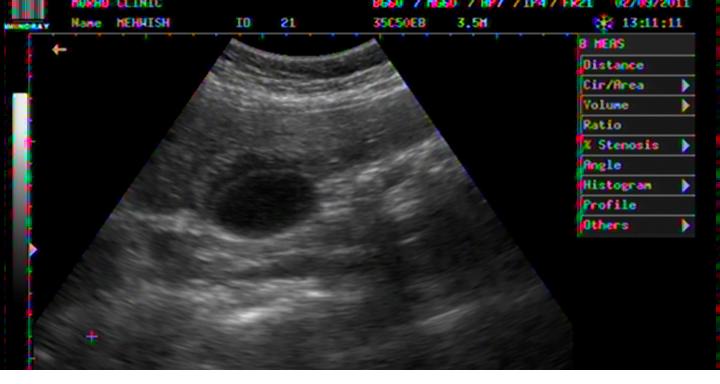

PERICHOLECYSTIC FLUID COLLECTION IN DHF